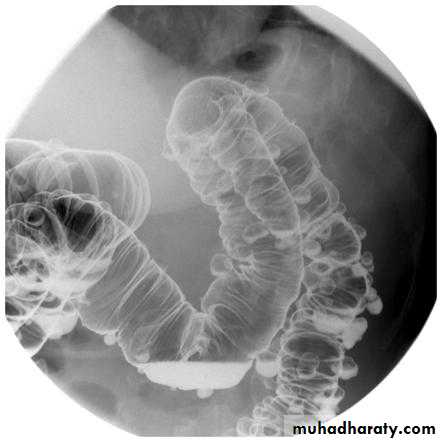

The valvulae conniventes (seen in proximal and mid small bowel) are always closer together than the colonic haustra and cross the width of the bowel , often giving "stack of coins" appearance

The colonic haustra ,which usually form incomplete bands across the colonic gas shadows, are always present in the ascending and transverse colon, but may be absent distal to the splenic flexure